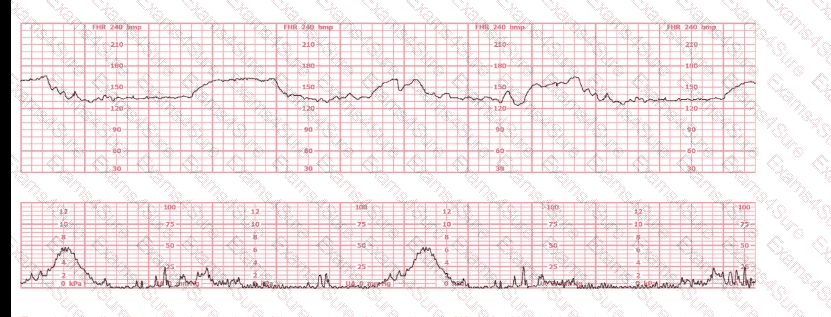

Based on the fetal heart rate tracing shown, the expected fetal pH would be: